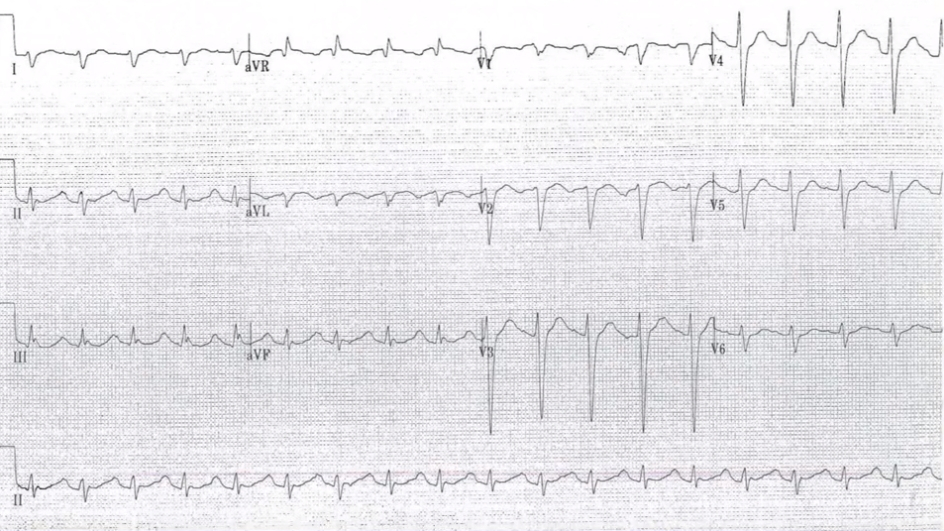

아래 심전도를 보면 이 특징들이 모두 있습니다.

ECG with TCA poisoning: Initial presentation

These are a series of electrocardiograms (ECGs) obtained from a patient with tricyclic antidepressant overdose. The first (above) shows the initial ECG demonstrating QRS interval prolongation and characteristic changes in AVR. The second (Severe cardiac toxicity) shows worsening changes consistent with progression of cardiac toxicity. Note the increases in the QRS interval and the R wave in AVR. The third (After treatment) shows narrowing of the QRS complex but persistent right axis deviation of the terminal 40 milliseconds following the initiation of treatment. The final ECG (Resolution) shows complete resolution of interval changes related to toxicity.